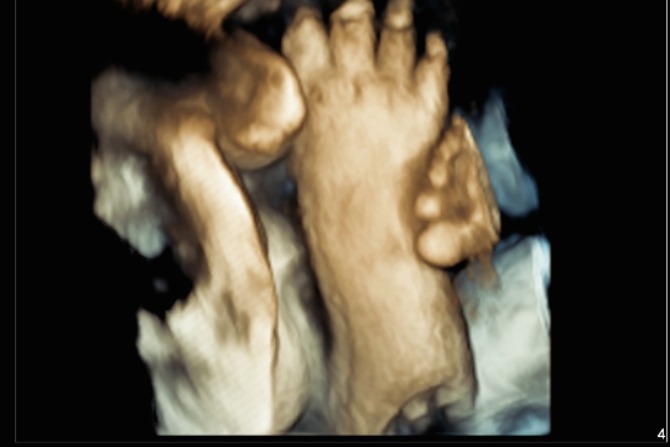

At this stage of the pregnancy, your baby has developed arms, legs, hands and feet, all which you will see moving. Baby can move all around the gestational sac, rolling onto its tummy or even standing on its head. Sonographers who perform these studies are required to undertake specific additional training.

Baby may not be able to fit across the screen as it did at the 12 week scan, but you will see movement such as swallowing, yawning, touching toes and even extending feet over its head.

This also gives an opportunity for the sonographer to show the mum how baby moves, the opening and closing of baby’s hands or taking a big yawn. You may even see a foot pressed up against mum’s belly.